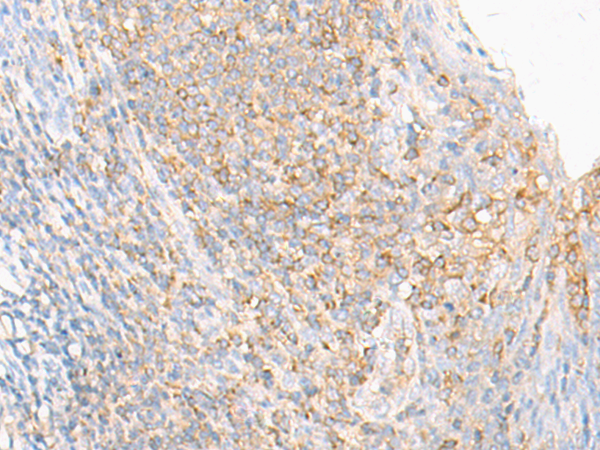

ELISA, IHC |

IHC positive control: |

Human tonsil |

IHC Recommend dilution: |

10-50 |